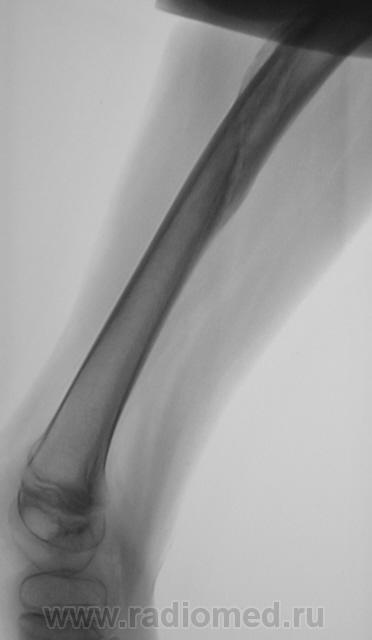

Пациент направлен на конрольное рентгенологическое исследование средней трети бедренной кости с целью оценки консолидации. Ранее - первичный снимок пациент был направлен на рентгенографию средней трети бедра, что и было сделано. Но, при производстве "контроля" рентгенолаборанты захватили тазобедренный сустав в прямой проекции, и возникли неясные сомнения по поводу головки, да и вообще...

Отлично все срослось. А что не нравится в головке? Остеопороз? Может быть после длительной иммобилизации.

Сама головка не нравится, особенно её нижне-медиальный отдел.

Согласна, что-то и меня в глазах головка бедра двоиться.

Пожалейте ребенка, не надо томографировать. Все укладывается в норму. Просто головка еще маленькая, а медиально - это шеечная шпора. Уж если не верите, снимите оба сустава одновременно.

Вероятно остеопороз головки от функционального щажения, разрушений не видно, капсула (мягкие ткани) параартикулярно - в норме...

Интересная дискуссия. Жаль с опозданием увидел (однако же, много времени уходит, пока всё на сайте просмотришь). На мой взгляд, патологии головки нет, без фрагментации, проекционно пересекается с тенью обызвествляемого Y-хряща. Под головкой медиально, несомненно, есть остеопороз, придающий нечеткость картине. Впрочем, регионарный остеопороз имеет место вследствие закономерной атрофии после иммобилизации. Сюда же наслаивается субстрат т.н. фигуры серпа, еще не оформленный. Впадина нормальная. Кость срослась - замечательно, всем бы такие результаты. Реабилитация обязательна.